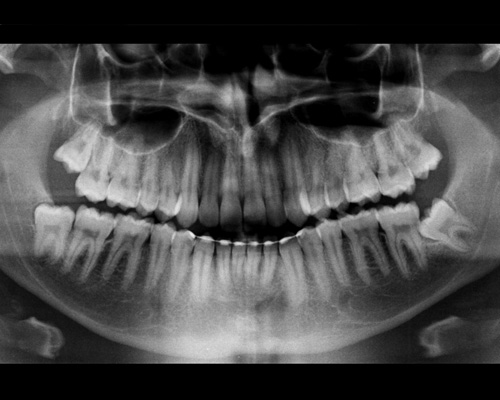

una radiografia delle arcate dentarie (che serve per verificare la presenza e la posizione dei denti decidui e permanenti)

Le radiografie vengono eseguite con strumenti digitali di ultima generazione che servono per sottoporre il giovane paziente alla minor dose radiogena oggi possibile.